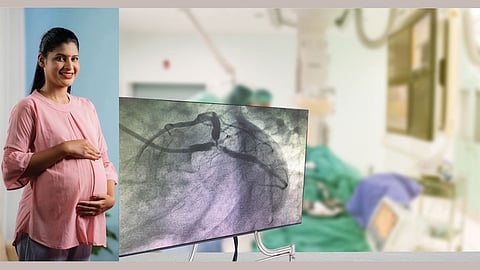

मला मागच्या वर्षी एकदम छातीत दुखायला लागले. डॉक्टरांकडे जाऊन तपासणी केली असता अँजिओप्लास्टी करण्याचा सल्ला दिला. अँजिओप्लास्टी केल्यावर परत तीन महिन्यांनी तशाच प्रकारचा त्रास होऊ लागला. तपासणी केल्यावर दुसऱ्या नसांमध्ये अवरोध असल्याचे आढळले. पुन्हा दुसरी अँजिओप्लास्टी केली. मी खरे म्हणजे आहार, दिनचर्या या सगळ्यांचे व्यवस्थित पालन करतो. पुढे परत असा त्रास झाला तर शस्त्रक्रियेशिवाय पर्याय नाही असे डॉक्टर म्हणतात. मला बाय पास वगैरे करायची इच्छा नाही. काही उपचार सुचवू शकाल का?

उत्तर - तुमच्या प्रश्र्नावरून रक्तदाब वगैरेंचा इतिहास कळू शकला नाही पण तरी आत्तापर्यंत दोनदा शस्त्रक्रिया झालेली आहे त्यामुळे यापुढे शस्त्रक्रिया टाळलेलीच बरे राहील. स्वतःची योग्य काळजी घेण्याच्या दृष्टीने व शरीरात रक्तप्रवाह व्यवस्थित राहावा या दृष्टीने रोज सकाळी स्नानापूर्वी संपूर्ण शरीराला संतुलन अभ्यंग सेसमी सिद्ध तेल नक्की लावावे. सकाळ-संध्याकाळ न चुकता हृदयासाठी उत्तम असलेले संतुलन सुहृदप्राशसारखे रसायन नक्की खावे.

मधुमेहाचा इतिहास असला तर त्यादृष्टीने आहाराची काळजी घेणे आवश्यक. बाहेरचे अन्न, जंक फूड वगैरे टाळणे इष्ट. सकाळ-संध्याकाळ घरचा सात्त्विक आहार घेणे जास्ती बरे. जेवणात २-३ चमचे घरी बनविलेले आयुर्वेदिक पद्धतीने बनविलिले साजूक तूप खाण्यात ठेवावे. त्वरित तज्ज्ञांचा सल्ला घेऊन संतुलन शास्त्रोक्त पंचकर्मासारखे पंचकर्म करून शरीरशुद्धीनंतर हृद्बस्तीसारखे चांगले उपचार करून घेतलेले बरे.